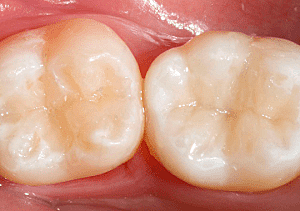

• Preparación para incrustación de las piezas 3.6 y 4.7

Preparación para incrustación de las piezas 3.6 y 4.7

Debido a que la extensión de diente que se tiene que restaurar es amplia se decidió en colocar incrustaciones. Se aísla, y se preparan las paredes de la cavidad de forma convergente. Finalmente se toman modelos y se obtura de forma provisional. El modelo se manda al laboratorio para poder realizar el diseño de la incrustación.

• Cementación de incrustación

Cementación de incrustación

Se prueban las incrustaciones en la cavidad y se cementan con cemento dual, se verifican los puntos de oclusión y se pulen.